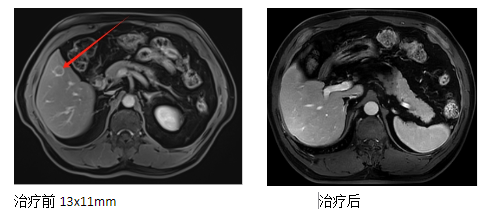

2.病史:患者于2021-12-31日我院体检,腹部核磁:肝硬化、肝S5段小肝癌。2022-01-04日行肝穿刺取检},病检结果提示:肝细胞肝癌,(肝脏肿物穿刺组织),免疫组化结果显示:CD34(+),CK19(小胆管+),CK7(小胆管+),Glypican-3(+),Hepatocyte(+),Ki-67(阳性率约15%),建议患者行手术治疗,患者及家属因手术风险大拒绝,后于2022年01月在我科行碳离子放疗,DT:PTV:45GyE/10fx,iTV补量15GyE/10fx。后规律复查病灶消失。

肝癌碳离子放疗 总剂量60Gy(RBE)/10Fx